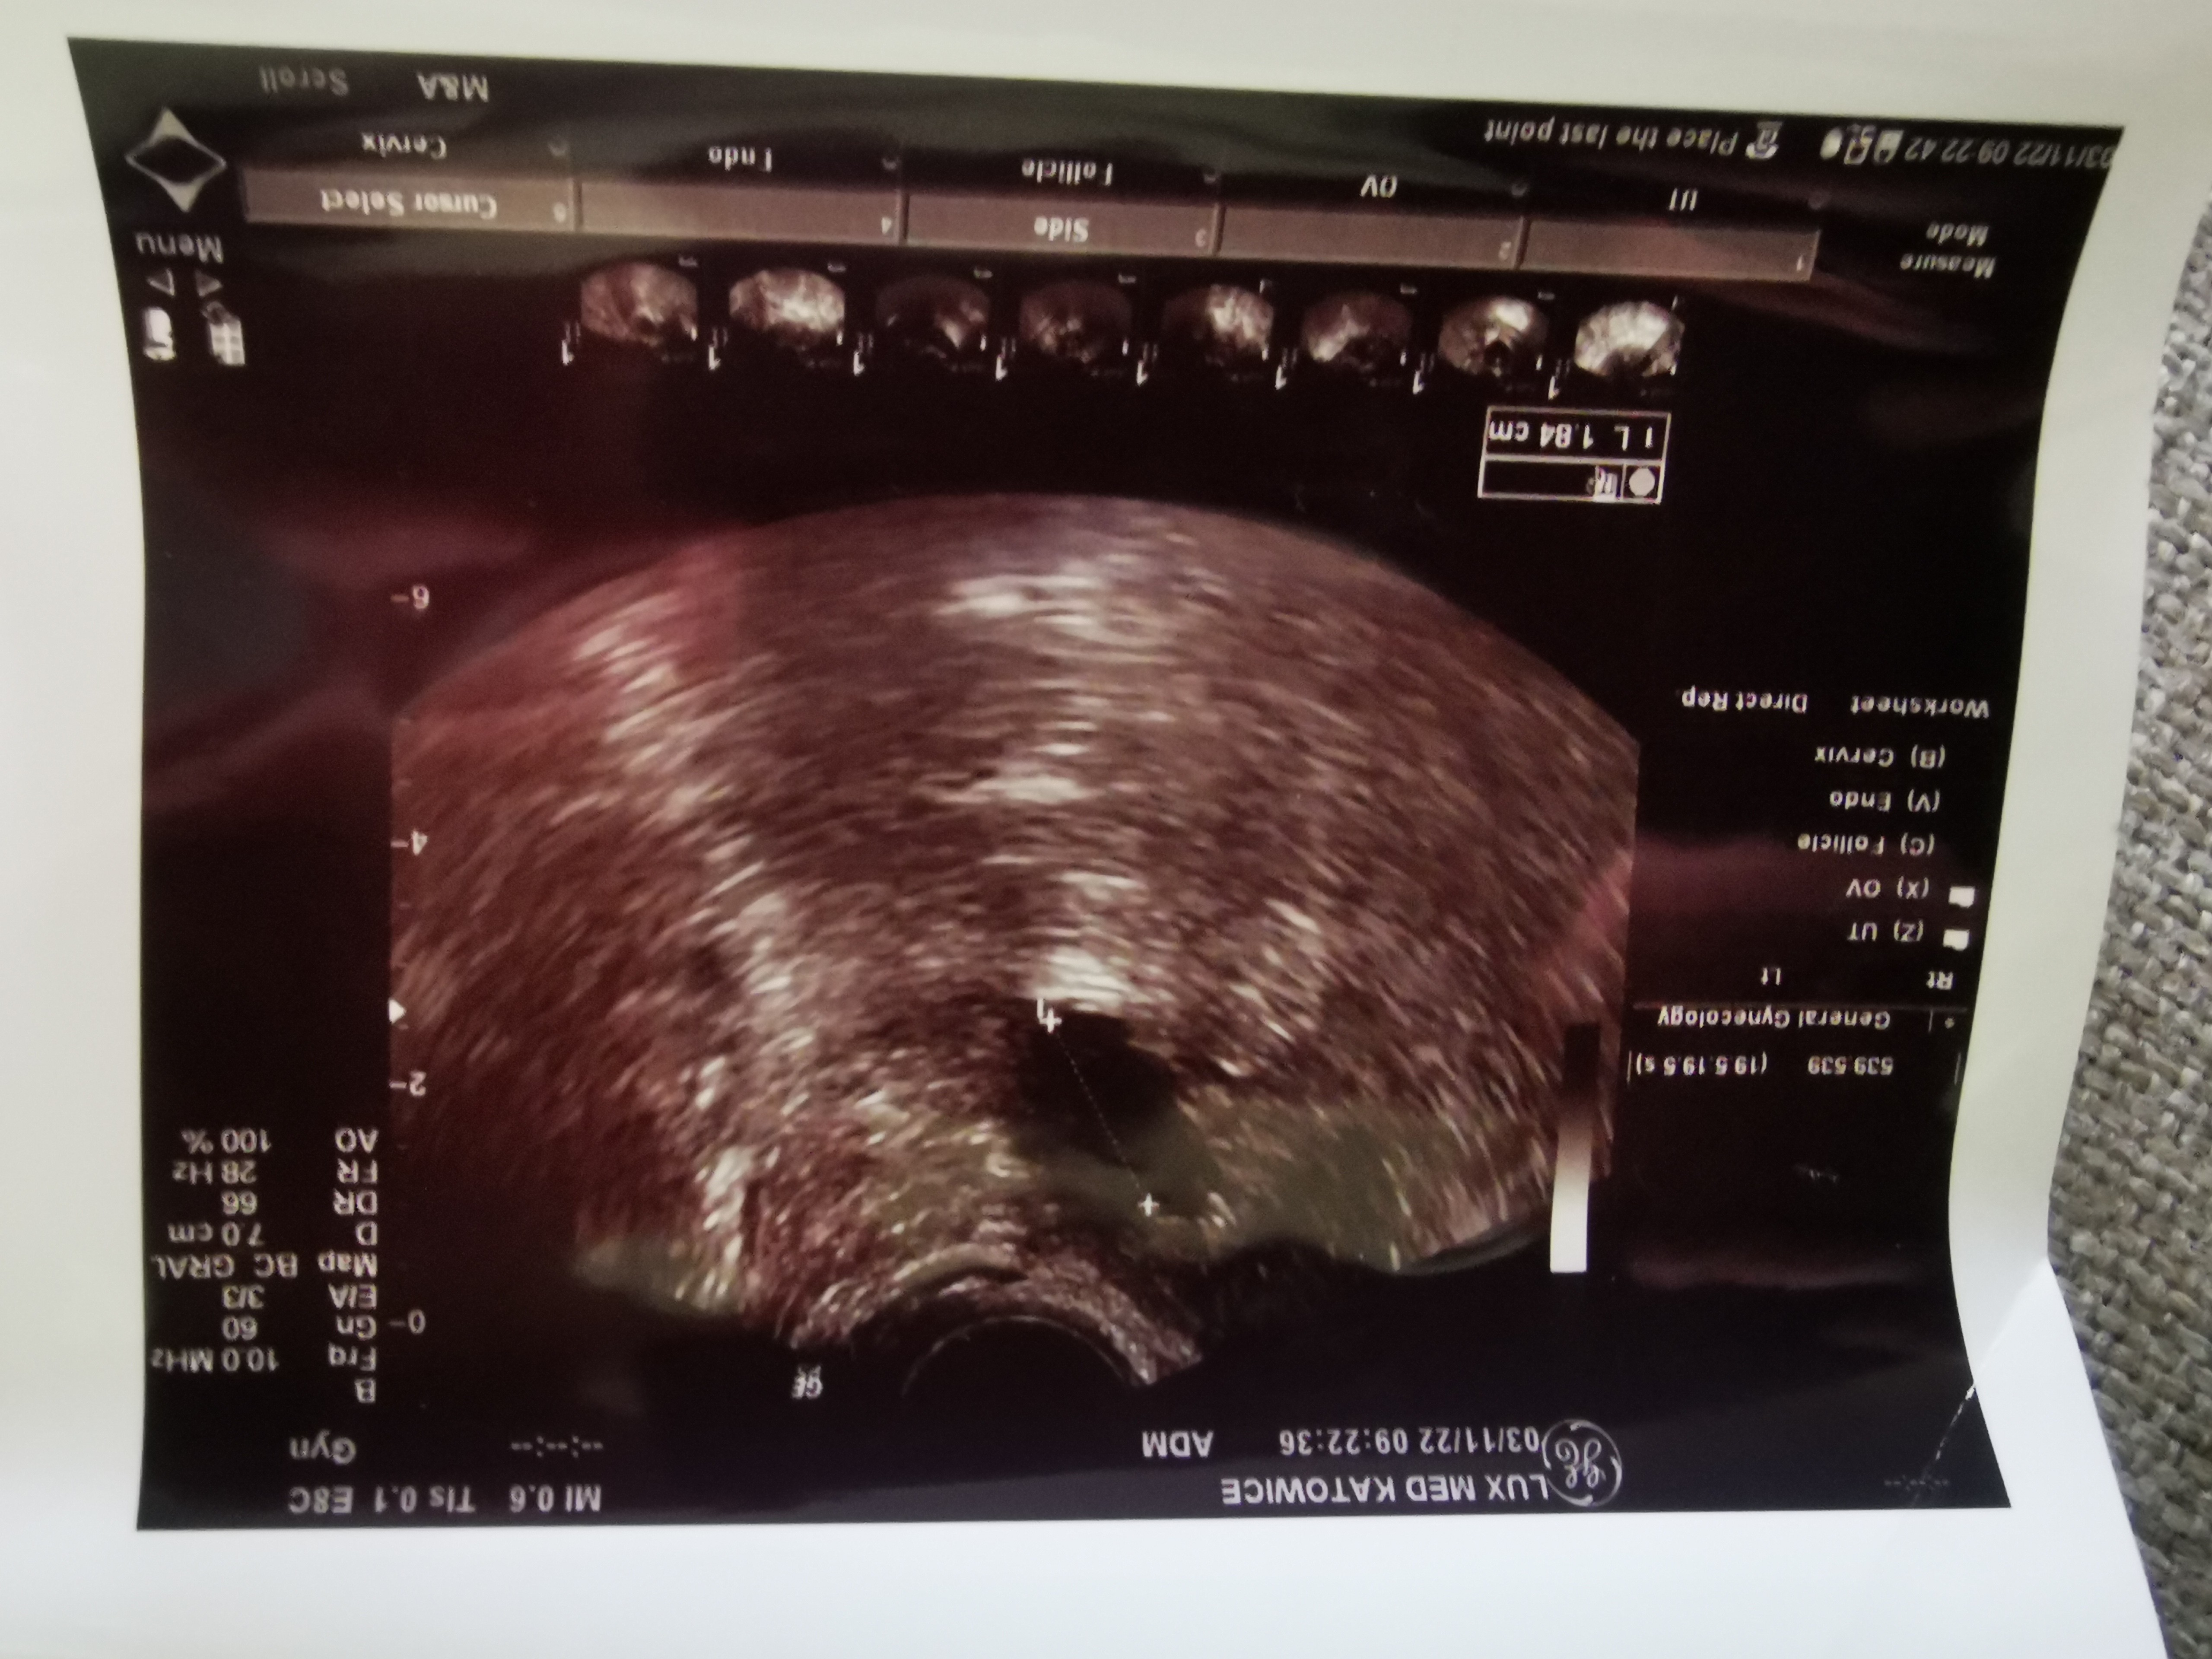

Zrobię jutro proga, bo jak badałam 3 listopada to był <0.1 i żadnych dominujących pęcherzyków.

Mam to trzymać do następnej wizyty 😂 to z 3 listopada. W ogóle nic nie kumam 😂🤷‍♀️, ale dla porównanie przy następnym monitoringu🤷‍♀️